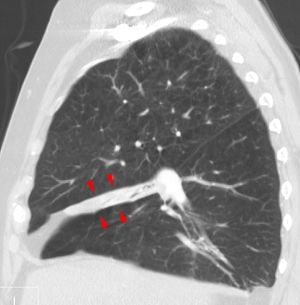

همود الرئة في الفص الأوسط من الرئة.

انخماص الرئة قد يكون حالة حادة أو مزمنة؛ في الحالات الحادة تكون الرئة قد حدث لها طي (انهارت) مؤخراً و يكون فقدان الهواء فقط هو الخاصية المميزة. وفي الحالات المزمنة غالباً ما تتميز المنطقة المتضررة بخليط معقد من فقدان الهواء و العدوى و توسع الشعب الهوائية وتدمر وتليّف الرئة.

الهمود المزمن

الانخماص المزمن قد يتخذ واحداً من الشكلين: إما متلازمة الفص الأوسط أو انخماص مدوّر. في متلازمة الفص الأوسط الأيمن، الفص الأوسط للرئة اليمنى ينقبض عادة بسبب الضغط على الشعب الهوائية من الغدد اللمفاوية المتضخمة أو وجود ورم أحياناً، و من الممكن أن تصاب الرئة المقبوضة المسدودة بالتهاب رئوي يفشل في التحلل تماماً ويؤدي إلى التهاب مزمن وتليف وتوسع الشعب الهوائية.